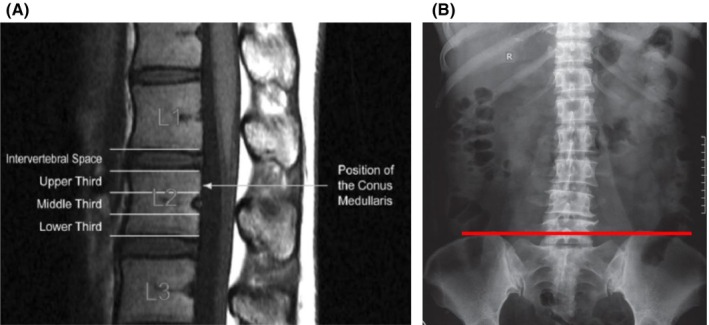

Background: Classic teaching is that spinal anesthesia is safe at or below the L2-L3 interspace. To evaluate this, we sought to determine the percentage of individuals with a conus medullaris termination (CMT) level at or below the L1-L2 interspace. Further, the relationship of CMT level to age, sex, body mass index (BMI), and spinal pathology was examined, as was the reliability of using Tuffier's line (TL) as an anatomical landmark.

Methods: This retrospective study evaluated magnetic resonance images of 944 adult patients to determine the CMT level. The relationship between age, sex, height, BMI, and spinal pathology and CMT level was explored by logistic regression. The correspondence of the TL line to the L4-L5 interspace and the presence of overlap with the CMT were examined using 720 lumbar x-rays of the same patient cohort.

Results: Of 944 patients (mean age, 57.8 years; 49% male), 18.9% had CMT at or below the L1-L2 interspace, and spinal anesthesia at the L2-L3 interspace was found to carry a 0.7% incidence of neuraxial risk. Only the presence of congenital spinal abnormalities was found to be significantly predictive of having a CMT at or below the L1-L2 interspace. TL was found to correspond to the L4-L5 interspace in 99.8% of patients with lumbar x-rays.

Conclusions: Spinal anesthesia at the L2-L3 interspace, using TL as an anatomical landmark, is safe in >99% of patients. However, caution must be exercised in all patients as demographic variables were found to be limited in predicting a low CMT level.